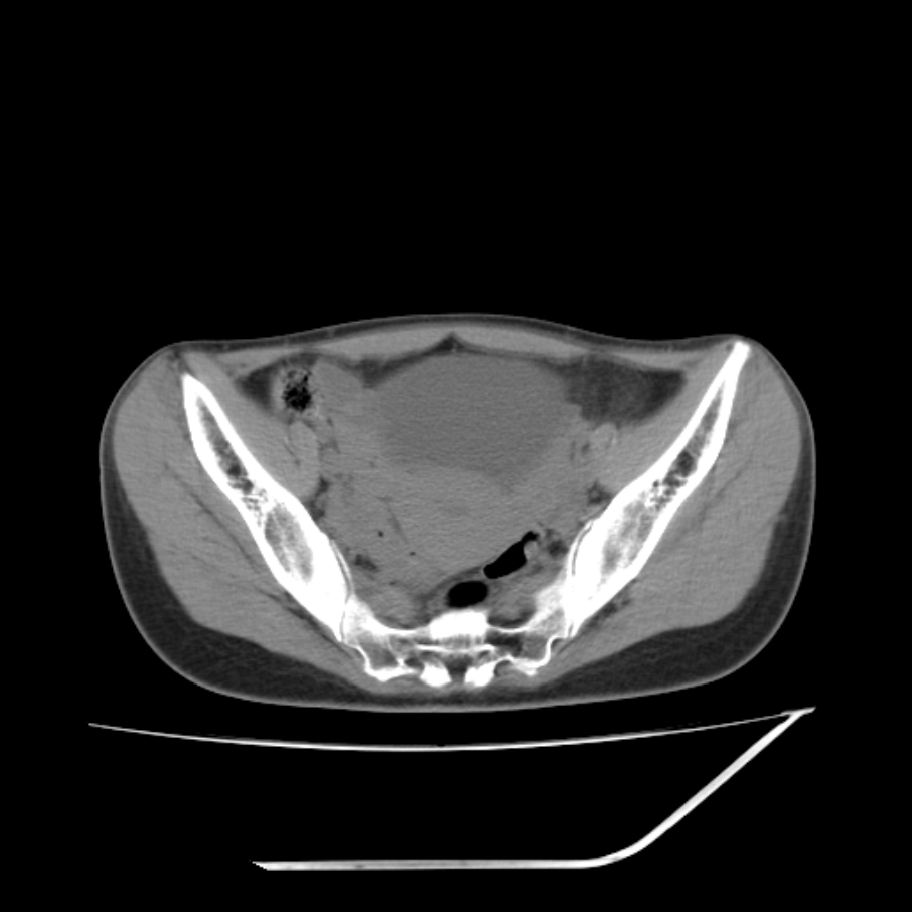

女,25岁。偶尔有右下腹不适感,余无明显异常。(结婚半年),囊壁较厚,是卵巢囊肿吗?

其上一层面见两枚小气泡影,考虑为肠管影可能,不完全除外囊肿

右侧卵巢区椭圆形囊性肿物,内壁光滑 无分隔。直肠子宫间隙内有少量积液征象。结合临床考虑卵巢巧克力囊肿,还要问问有没有痛经,本例ct怎么没有灌肠?要是灌肠或前一前口服造影剂,起码可以和肠管区别开

b超示:囊实性占位,畸胎瘤?临床有痛经。

考虑右侧卵巢囊性占位性病变(巧克力囊肿?),盆腔积液有不排除宫外孕可能,请结合临床和b超。

右侧卵巢囊伴盆腔少量积液。